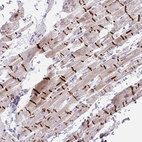

Immunohistochemical staining of human heart muscle shows strong membranous positivity in myocytes / Intercalated disc distinctly stained.